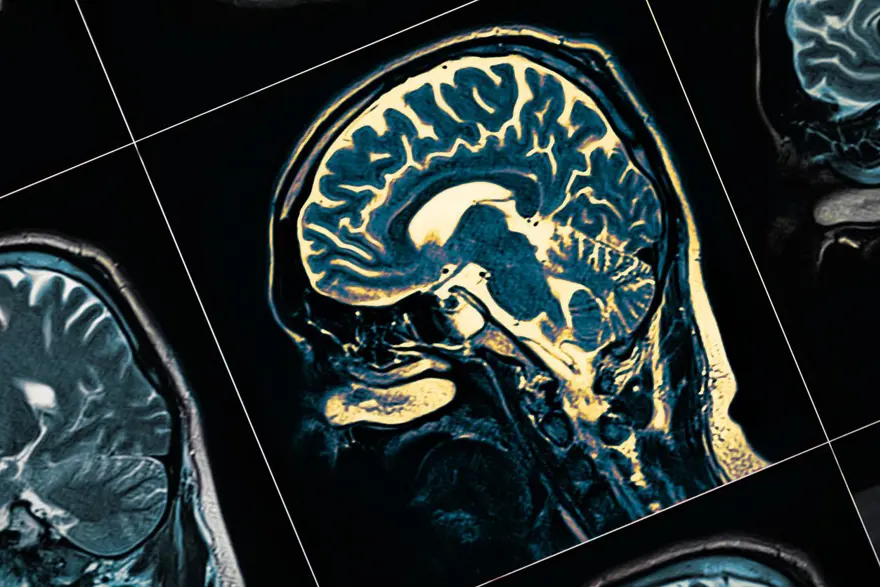

Alzheimer'ı 10 yıl daha erken teşhis etmek mümkün mü?

Bilim insanları, Alzheimer'ın basit bir kan testi ile erken evrelerde tespit edilebileceğini öngörüyor. 50 bin katılımcının inceleneceği çalışmada, yalnızca Alzheimer'ın değil, kalp krizi ve kanser gibi ciddi sağlık sorunlarının da yıllar öncesinden belirlenebileceği ileri sürülüyor.